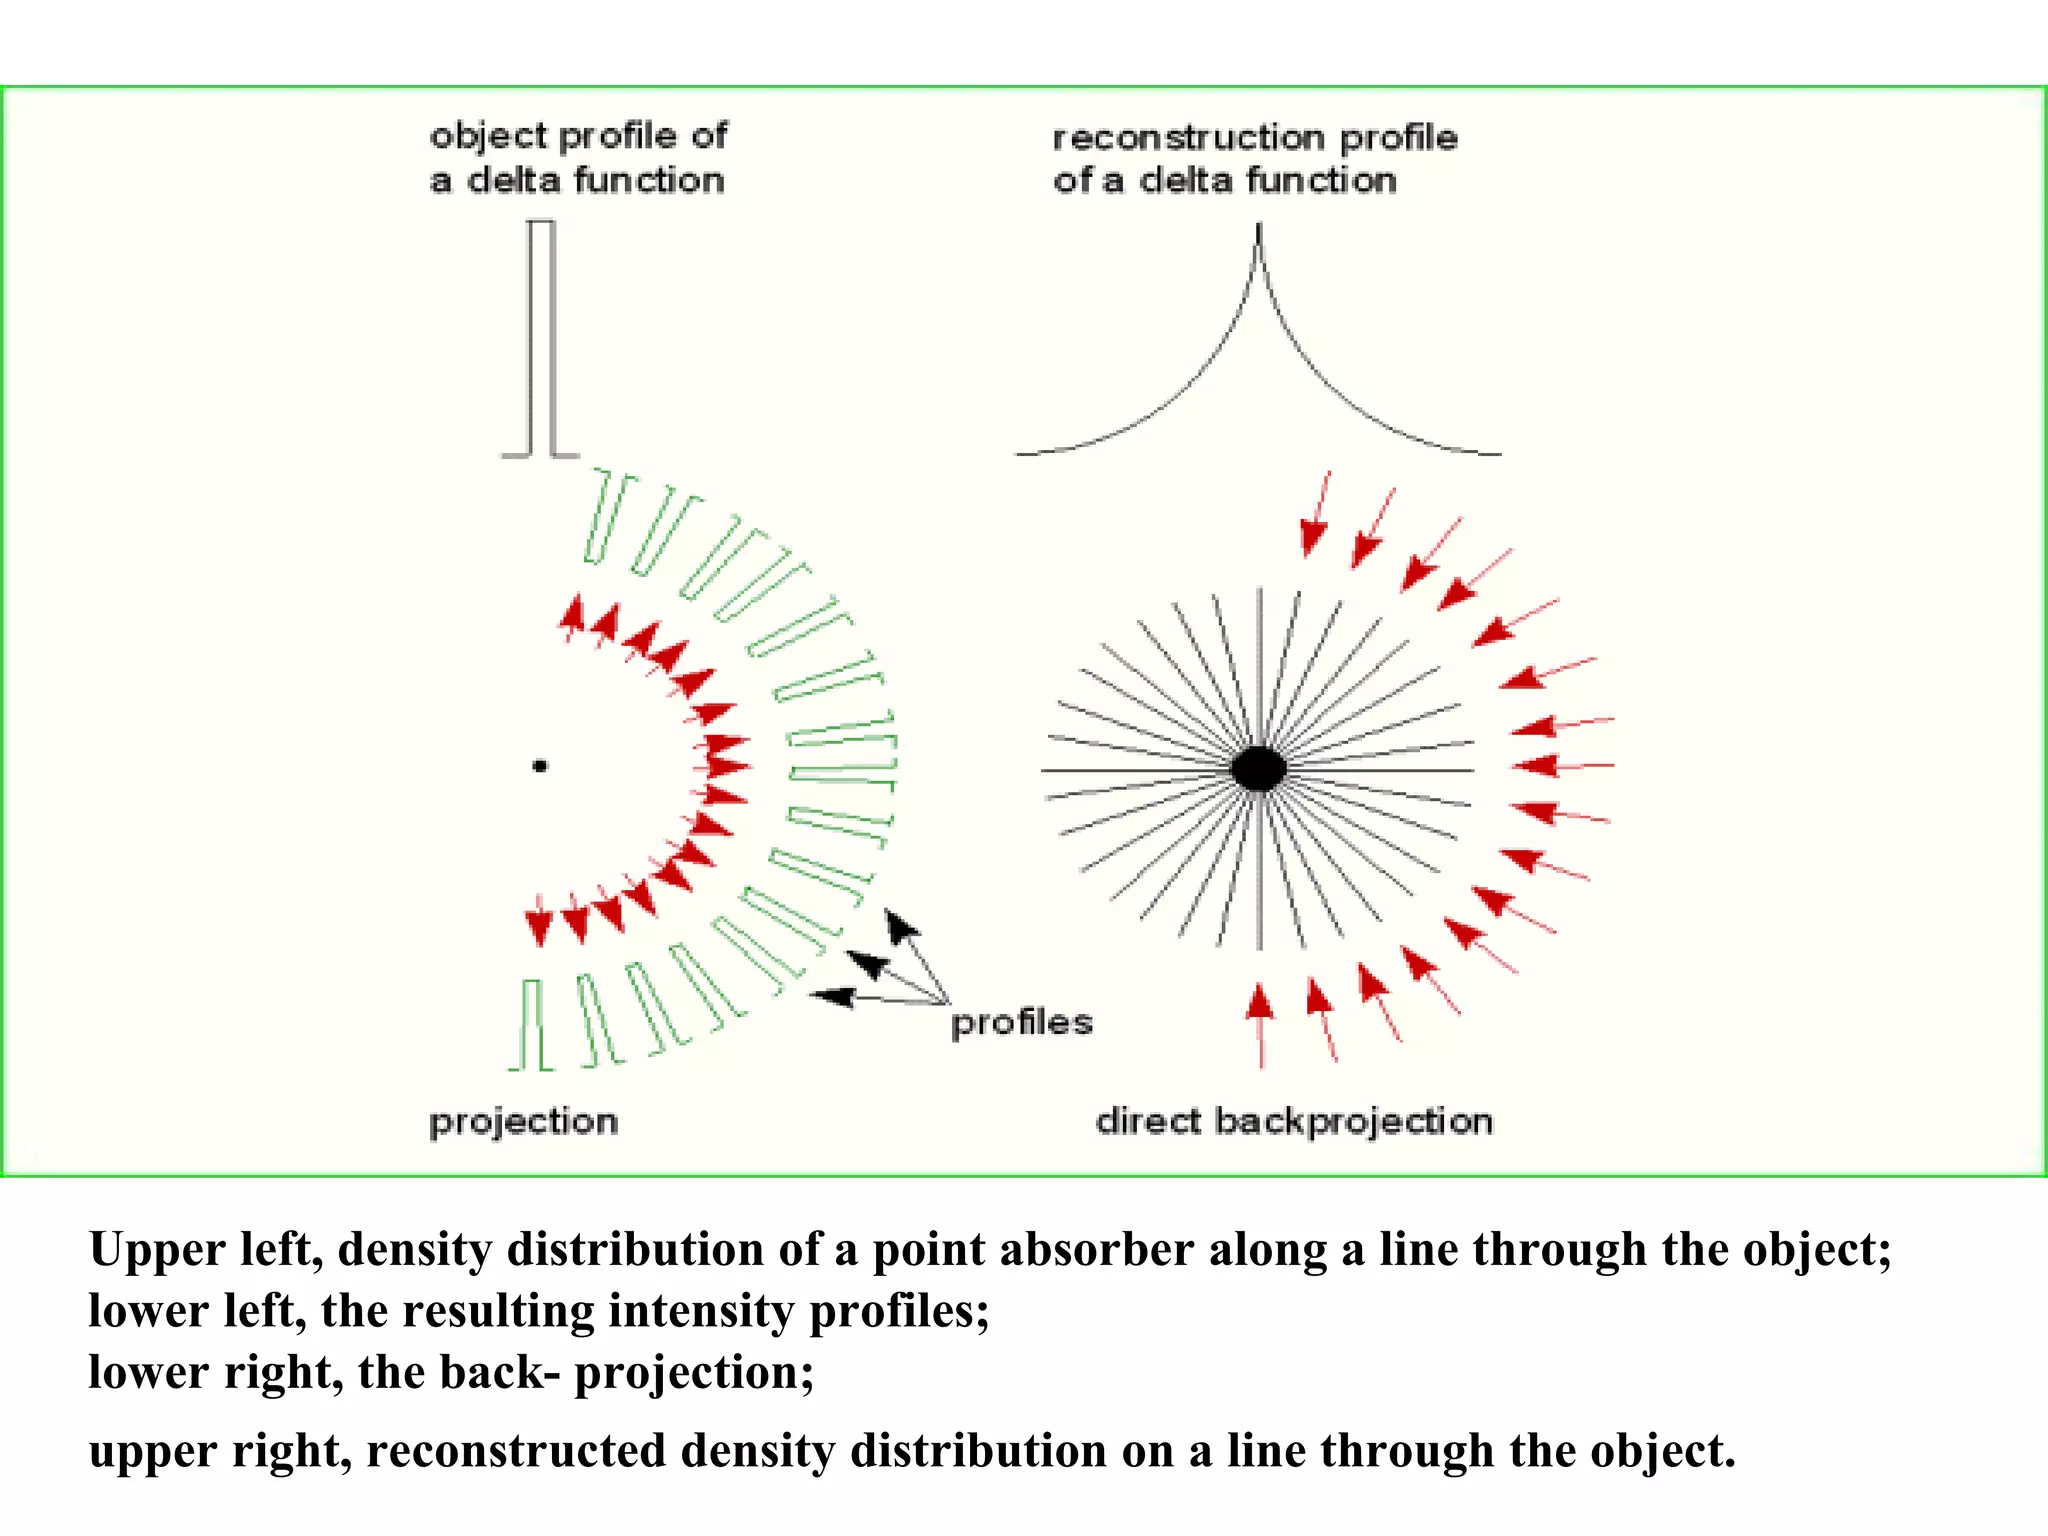

The document discusses various medical imaging modalities including x-rays, computed tomography (CT), and digital mammography. It describes the basic principles and historical development of these technologies, how images are formed, and what types of anatomical features and abnormalities they can detect. Key advances include the development of digital systems that allow image manipulation and remote consultation. While promising, digital mammography still faces challenges around resolution and cost.